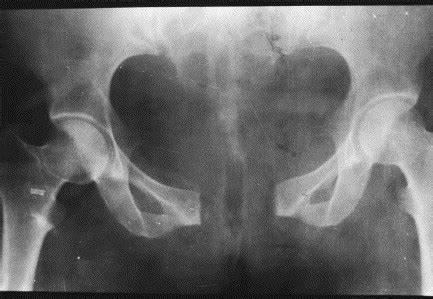

什么是耻骨联合分离?

耻骨联合分离症是指骨盆前方两侧耻骨纤维软骨联合处,因外力而发生微小的错移,表现耻骨联合距离增宽或上下错动出现局部疼痛和下肢抬举困难等功能障碍的软组织损伤性疾病。

耻骨联合分离示意图

耻骨联合一般在怀孕三个月后开始变宽,统计显示,约31.7%孕妇产妇有耻骨联合处疼痛或不适,其中早孕期发生率约为12%,中孕期发生率约为34%,晚孕期高达52%。